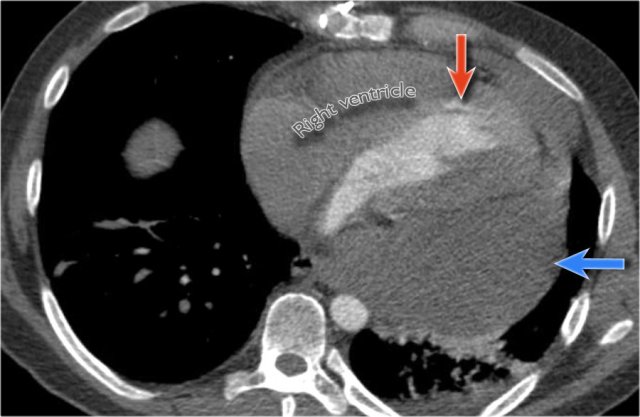

Pericardial effusion

Whenever we encounter a large heart figure, we should always be aware of the possibility of pericardial effusion simulating a large heart.

On the chest x-ray it looks as if this patient has a dilated heart while on the CT it is clear, that it is the pericardial effusion that is responsible for the enlarged heart figure.

Especially in patients who had recent cardiac surgery an enlargement of the heart figure can indicate pericardial bleeding.

This patient had a change in the heart configuration and pericardial bleeding was suspected.

Ultrasound demonstrated only a minimal pericardial effusion.

Continue with the CT.

There is a large pericardial effusion, which is located posteriorly to the left ventricle (blue arrow).

The left ventricle id filled with contrast and is compressed (red arrow).

At surgery a large hematoma in the posterior part of the pericardium was found.

Notice that on the anterior side there is only a minimal collection of pericardial fluid, which explains why the ultrasound examination underestimated the amount of pericardial fluid.